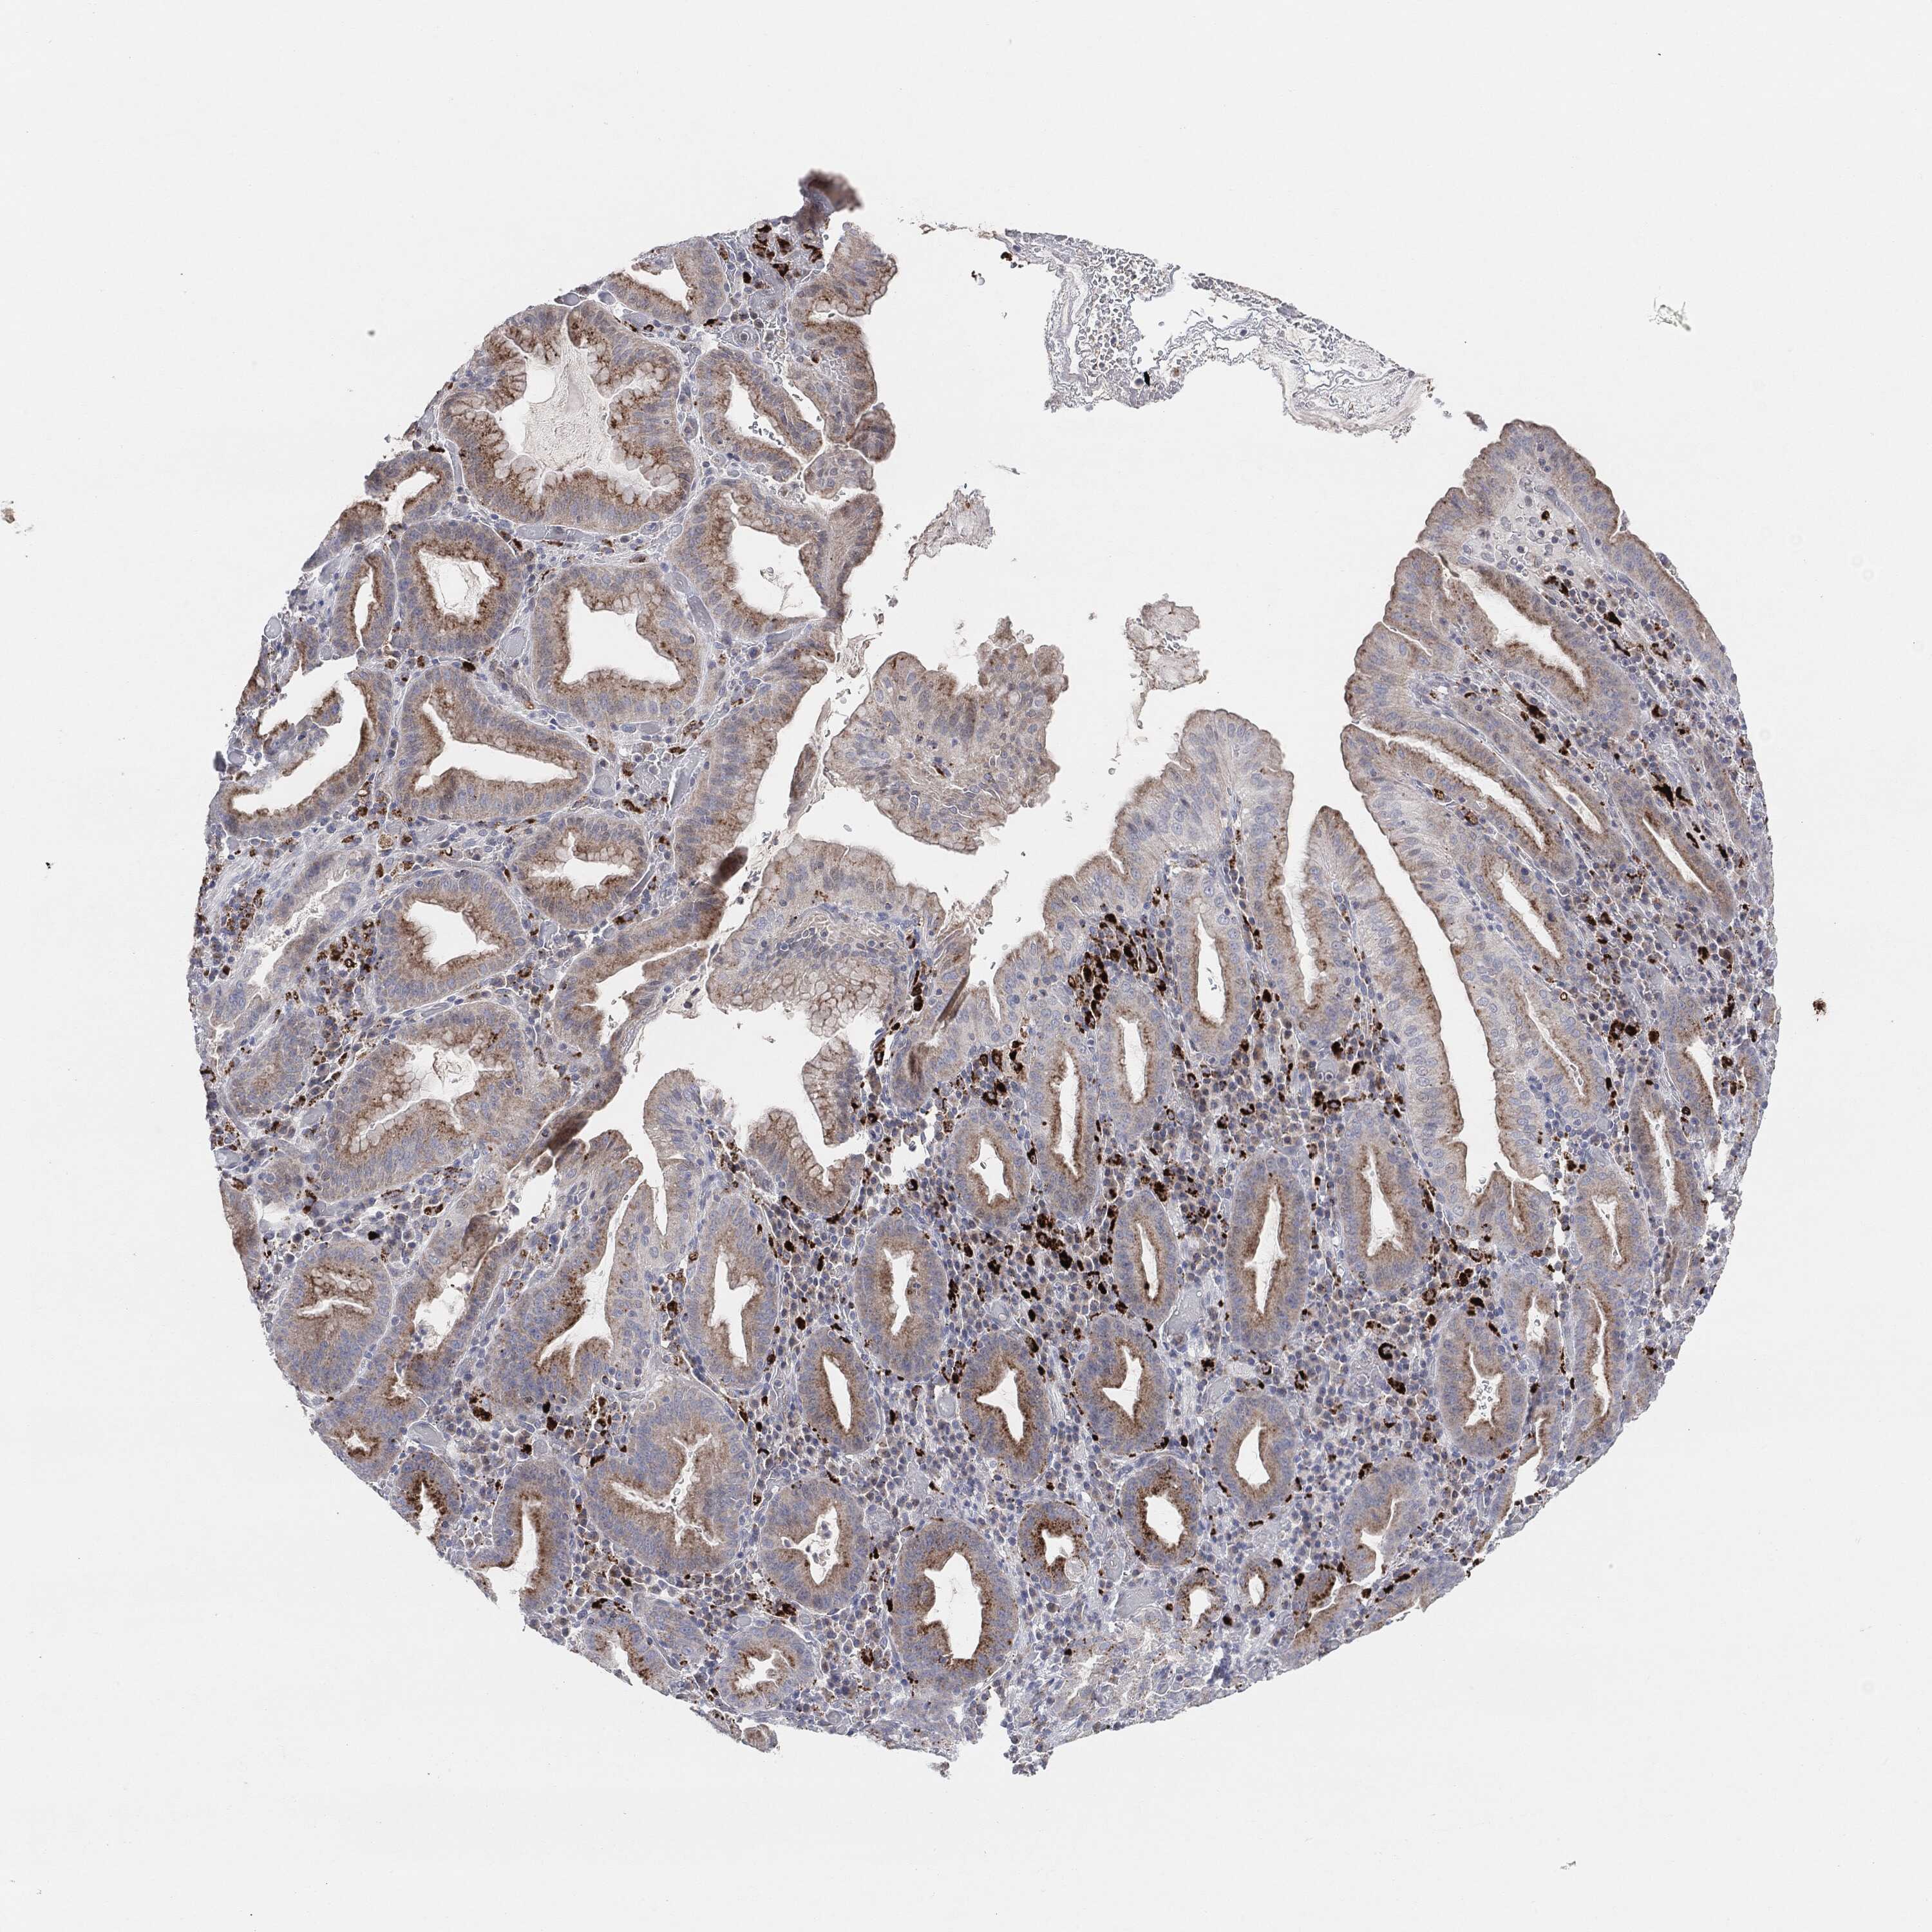

STOMACH CANCER - Protein expressioni

A mouse-over function shows sample information and annotation data. Click on an image to view it in a full screen mode. Samples can be filtered based on level of antibody staining by selecting one or several of the following categories: high, medium, low and not detected. The assay and annotation is described here.

Note that samples used for immunohistochemistry by the Human Protein Atlas do not correspond to samples in the TCGA dataset.

Antibody stainingi

Antibody staining in the annotated cell types in the current human tissue is reported as not detected, low, medium, or high, based on conventional immunohistochemistry profiling in selected tissues. This score is based on the combination of the staining intensity and fraction of stained cells.

Each image is clickable and will lead to virtual microscopy that enables deeper exploration of all samples and also displays staining intensity scores, fraction scores and subcellular localization as well as patient and tissue information for each sample.

Antibody HPA031634

Antibody CAB080501

Antibody CAB080502

Antibody CAB080503

Adenocarcinoma, NOS

Adenocarcinoma, High grade